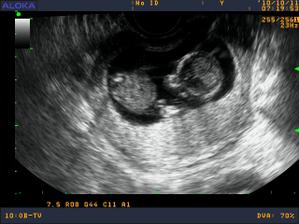

Moje brusko od zaciatku do konca

zacinam 11 tyzdnom, a vykukajucim pupikom